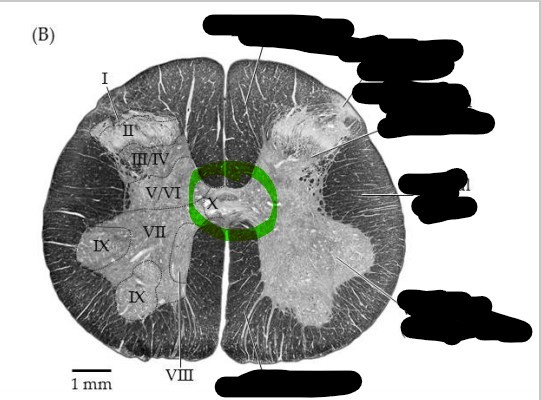

Spinal cord - gray matter

centrally located, and its shape resembles an H or a butterfly; subdivided into anterior horns, lateral horns, posterior horns, and gray commisure

Spinal cord - white matter

external to gray matter and partioned into three regions, posterior, anterior, and lateral funiculus

Spinal cord - dorsal horn

left and right posterior masses of gray matter; axons of sensory neurons and the cell bodies of interneurons located here

Spinal cord - ventral horn

left and right anterior masses of gray matter; primarily house the cell bodies of somatic motor neurons which innervate skeletal muscle

Spinal cord - gray commissure

horizontal bar of gray matter that surrounds the central canal; primarily contains unmyelinated axons and serves as a communication route between the right and left sides of the gray matter

Spinal cord - central canal

hollow tube that runs the length of the spinal cord; filled with cerebral spinal fluid